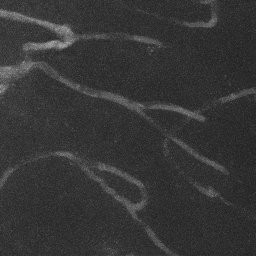

Semantic segmentation of blood vessels is an important task in medical image analysis, but its progress is often hindered by the scarcity of large annotated datasets and the poor generalization of models across different imaging modalities. A key aspect is the tendency of Convolutional Neural Networks (CNNs) to learn texture-based features, which limits their performance when applied to new domains with different visual characteristics. We hypothesize that leveraging geometric priors of vessel shapes, such as their tubular and branching nature, can lead to more robust and data-efficient models. To investigate this, we introduce VessShape, a methodology for generating large-scale 2D synthetic datasets designed to instill a shape bias in segmentation models. VessShape images contain procedurally generated tubular geometries combined with a wide variety of foreground and background textures, encouraging models to learn shape cues rather than textures. We demonstrate that a model pre-trained on VessShape images achieves strong few-shot segmentation performance on two real-world datasets from different domains, requiring only four to ten samples for fine-tuning. Furthermore, the model exhibits notable zero-shot capabilities, effectively segmenting vessels in unseen domains without any target-specific training. Our results indicate that pre-training with a strong shape bias can be an effective strategy to overcome data scarcity and improve model generalization in blood vessel segmentation.